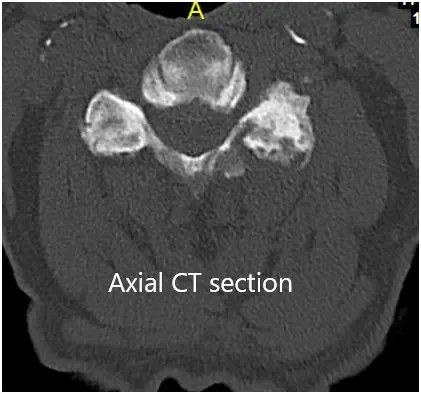

La TC de la columna cervical mostró protrusiones discales posteriores de varios niveles con estenosis foraminal neural bilateral de la columna cervical media a baja. Los cambios degenerativos hipertróficos escleróticos se asociaron con las facetas cervicales medias a bajas.

TAC coronal y axial preoperatorio.